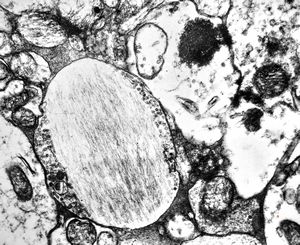

F,49y. | purulent meningitis- meningococcal v.s.

F,49y. | purulent meningitis- meningococcal v.s.

F,49y. | purulent meningitis- meningococcal v.s.